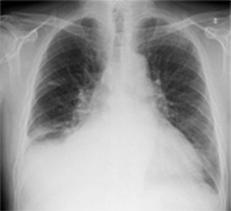

左肺尖部に濃度の上昇がありますが、通常画像では淡い変化の為、直ぐに気づきません。読影が難しい肺尖部の鎖骨裏などでも経時差分画像で即座に変化を確認できます。